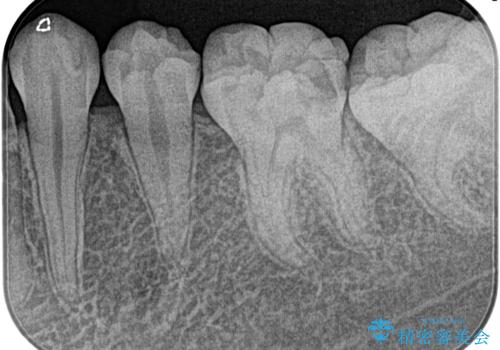

奥歯がズキズキ痛い 根管治療

担当医 河口智英